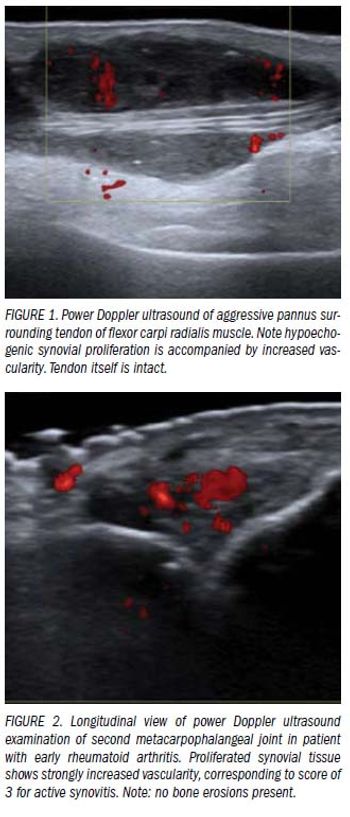

Rheumatoid arthritis is a chronic and progressive inflammatory disease of the joints.